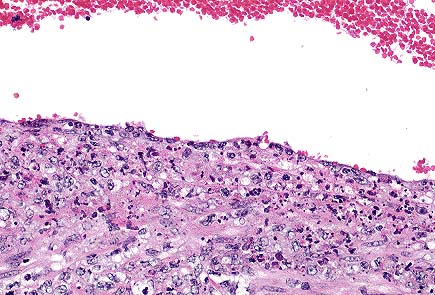

Placental necrosis in a 3-year-old Cuvier's gazelle (HE, 100X, 31K).

Higher magnification of the above field. The bluish haze within the cytoplasm of this trophoblast are numberous intracellular coccobacilli compatible with Coxiella burnetti. (HE, 400X, 21K)

Significant lesions were limited to the placenta. Several epithelial cells in areas of necrosis have fuzzy blue cytoplasm. Sections were stained with Gimenez method, which revealed <1 micron diameter red organisms within the cytoplasm. Organisms did not stain with Brown-Brenn Gram stain. Paraffin blocks were submitted to Washington Animal Disease Diagnostic Laboratory for immunohistochemistry. Sections were positive for Coxiella and negative for Chlamydia.

Conference Note: Microscopically, placental trophoblasts lining the cotyledonary villi are distended by small, approximately 1æm diameter, basophilic, intracytoplasmic organisms. The differential diagnosis for intratrophoblastic organisms in cases of placentitis includes Coxiella, Brucella, Campylobacter, and Chlamydia. Of these, only Coxiella burnetii and Chlamydia stain positively with Gimenez or modified acid-fast stains. The morphology of the intracytoplasmic organisms on Gimenez-stained sections should differentiate C. burnetii from Chlamydia since C. burnetii appear as pleomorphic, or thin, rod-shaped structures, while chlamydial elementary bodies are uniformly small and round. Some, but not all, sections examined by conference participants had a focal vasculitis of one of the larger placental vessels.